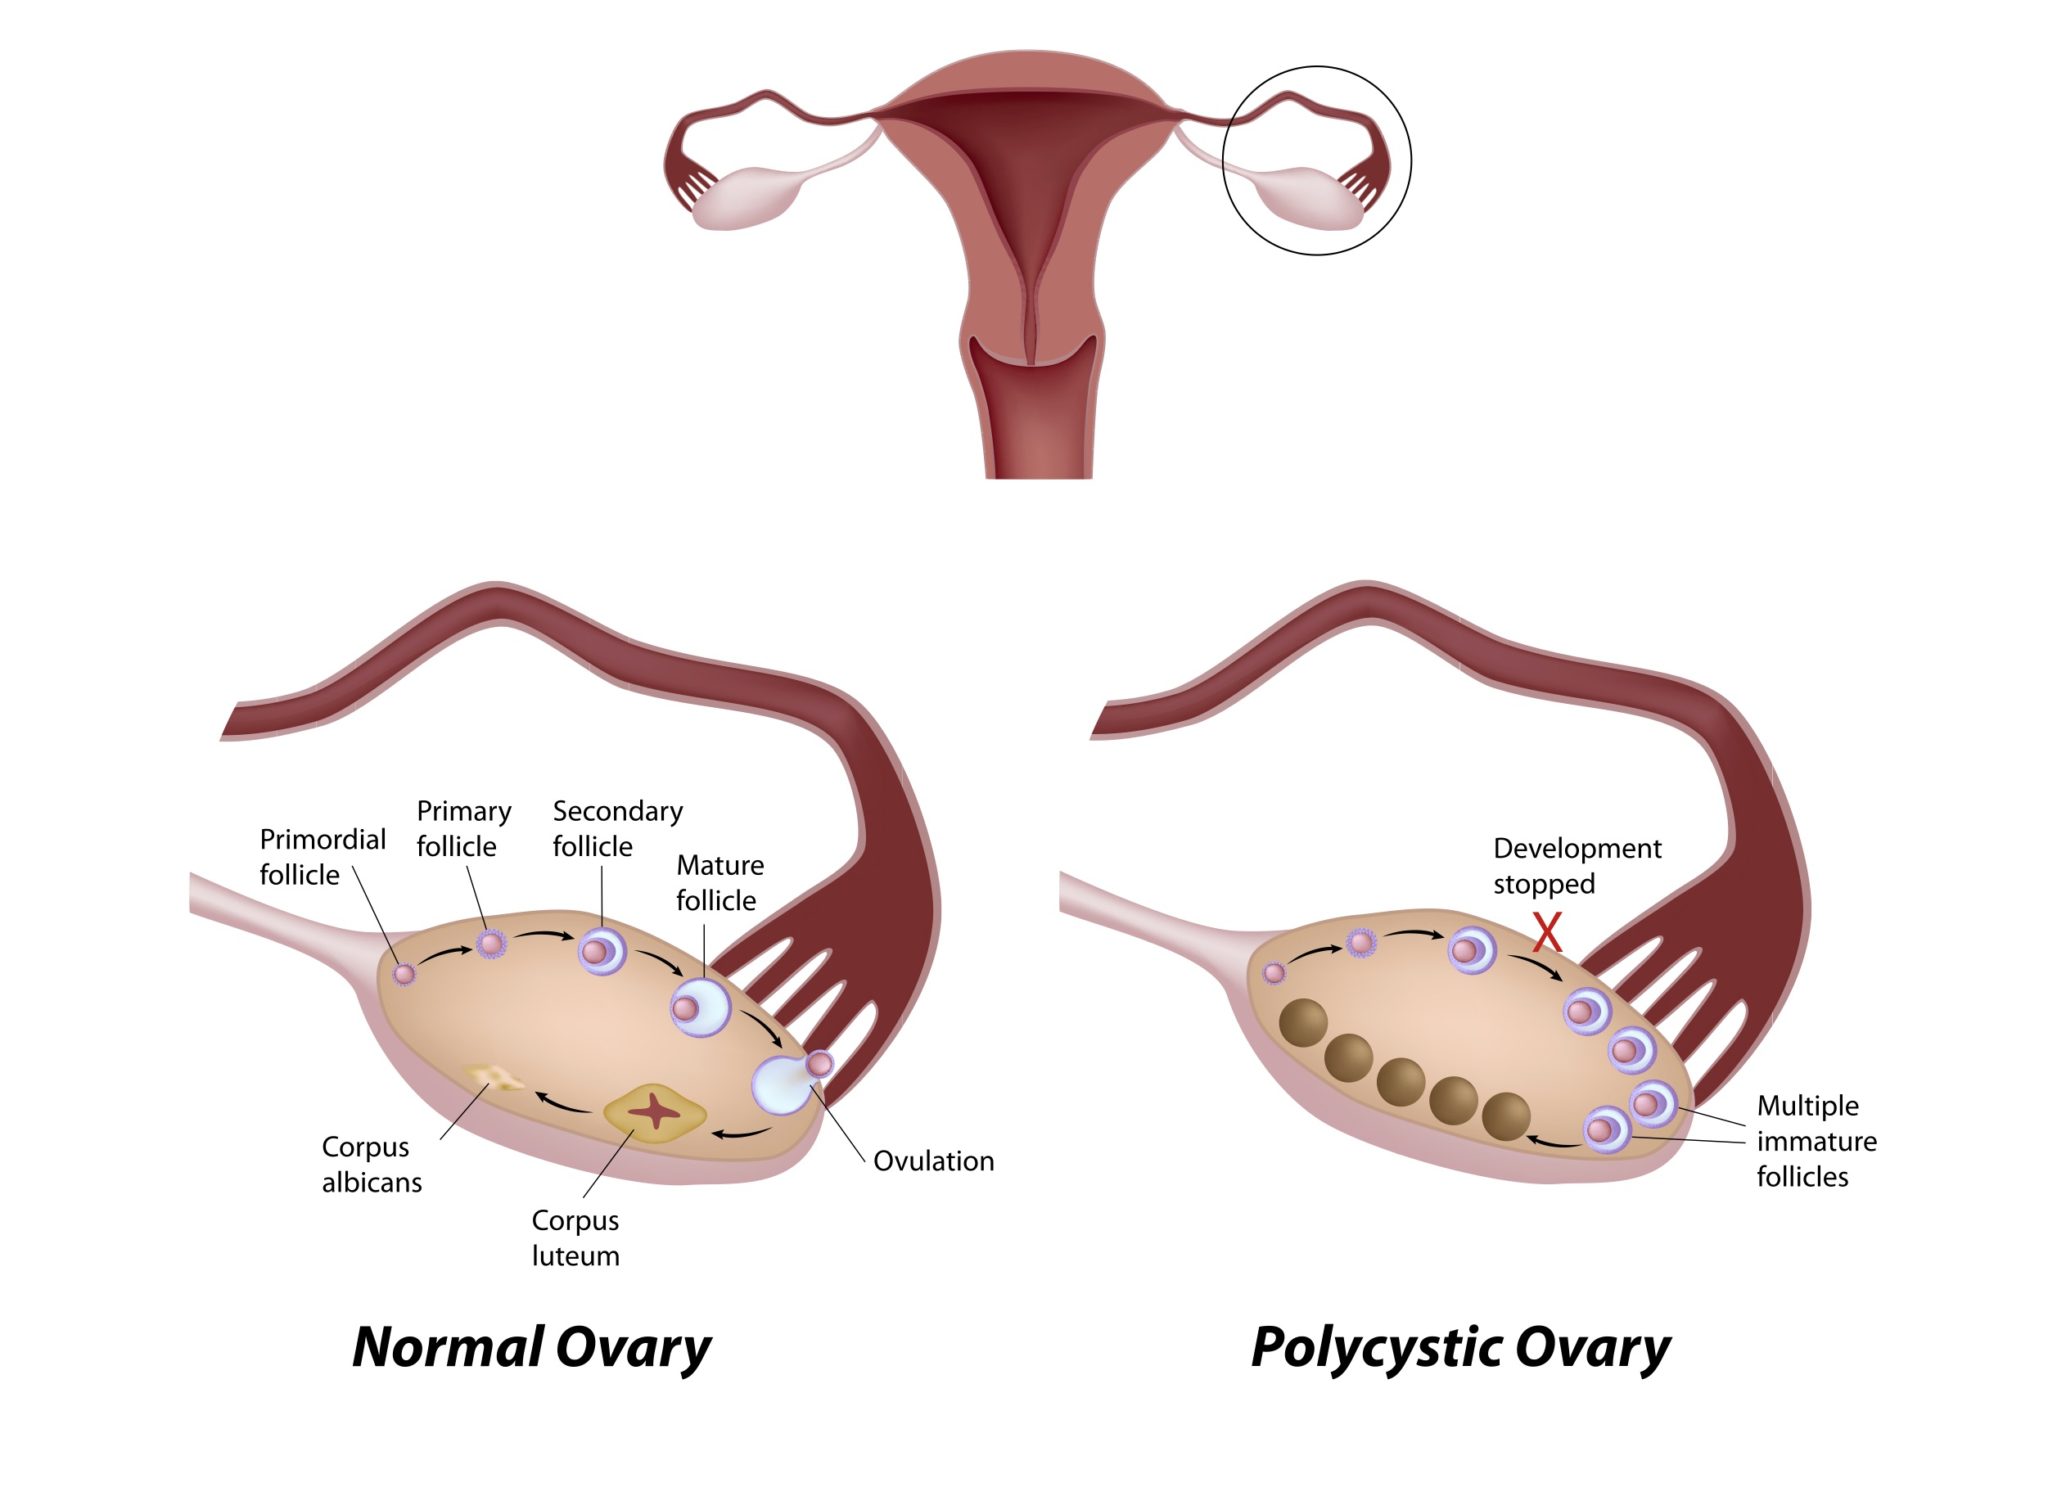

多嚢胞性卵巣症候群〜普段の生活で気をつけること 産婦人科専門医による妊活ガイド

多嚢胞性卵巣症候群(PCOS)でお悩みの方へ 大津市 医療法人 木下レディースクリニック

【多嚢胞性卵巣症候群】手術で治る?腹腔鏡下卵巣多孔術とは|Smile Life